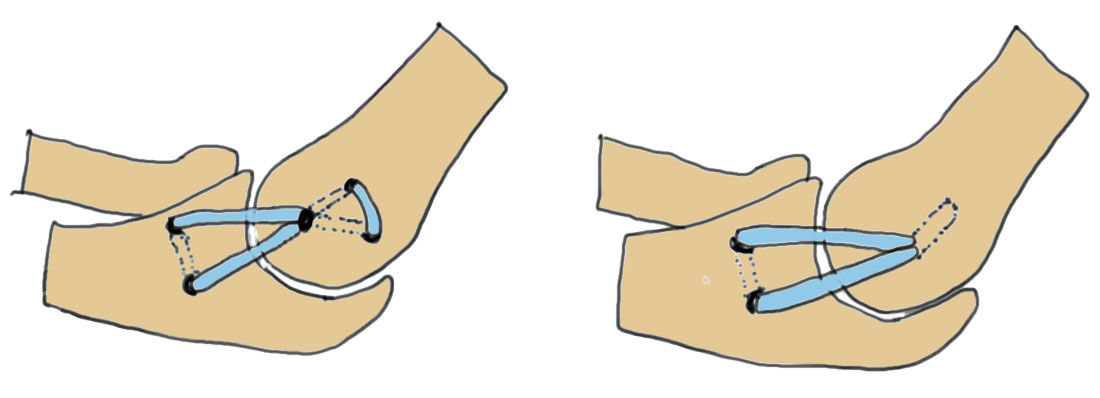

| Valgus stress test | Milking maneuver |

|---|---|

|

Patient supine

Elbow flexed 25 degrees (removes bony stability) - valgus stress and palpate UCL |

Patient seated or standing

Shoulder extended and externally rotated - thumb pointing out / wrist supinated - elbow at 90 debrees - pull on thumb and extend arm which places a valgus strain |

| Modified Jobes - patient prone | |

|

|